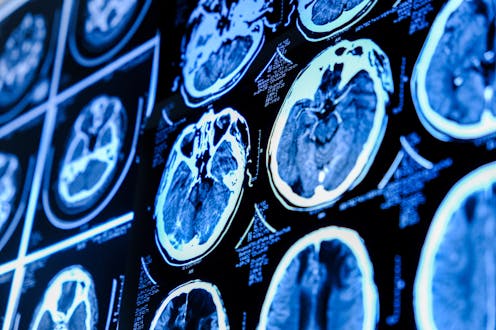

About three in 100 people will have a brain aneurysm, varying in size from less than 5mm to more than 25mm in diameter. The majority are only discovered while undergoing imaging for something else (for example, head trauma), because small aneurysms may not cause any symptoms.